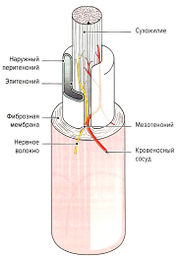

| 04:28, 19 июля 2016 | Mishci sport11.jpg (файл) |  |

63 КБ | Anes | Строение мышечно-сухожильного соединения | 1 |